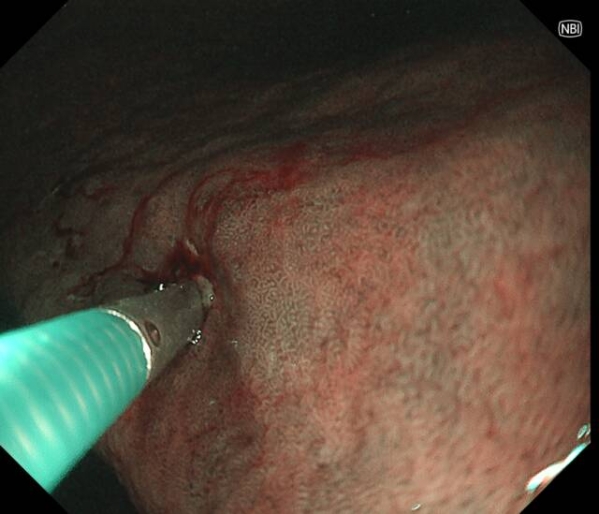

患者李先生(化名),60多岁,平日不抽烟不喝酒,无任何消化道症状,但有家族史,在子女的带领下来做胃肠镜精查。前两年刚做过胃肠镜,未发现异常。在新镜界精查中,发现胃角处有一黏膜与正常略微不同,经NBI+放大内镜放大观查,考虑胃早癌,活检证实为高级别上皮内瘤变。恰逢麻兴华教授(新镜界日方特聘专家)来院坐诊,于是由麻教授带领内镜团队行内镜下黏膜剥离术(ESD),术后患者痊愈。

因为是早期胃癌,在内镜下行黏膜剥离术(ESD),就能够治愈,无需外科手术及放化疗。这是不幸中的万幸,患者今后只需定期胃镜复查即可。